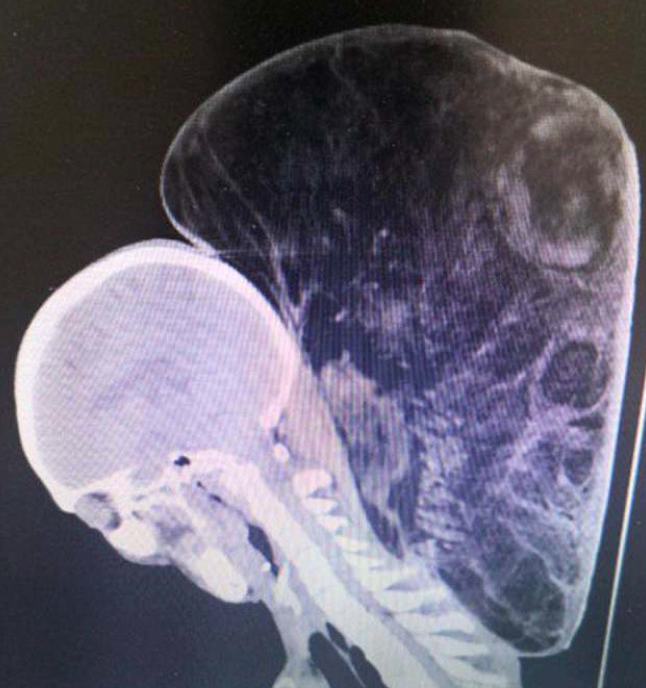

64 yaşındaki Zhao Xingfu, yıllarca boynunda büyümeye devam eden ve 15 kiloya kadar ulaşan tümörünü operasyonla aldırdı.

47 sene önce boynunun arka kısmıda çıkan yumurta büyüklüğündeki şişlik sebebiyle doktora giden Zhao Xingfu, ameliyatı pahalı ve "Acı hissiyatı nasıl olsa yok" diye tedaviyi kabul etmemiş, günlük yaşantısına geri dönmüştü. 64 yaşındaki Zhao Xingfu, yıllarca boynunda büyümeye devam eden ve 15 kiloya kadar ulaşan tümörünü operasyonla aldırdı.

Yıllar içinde boynundaki tümör büyüdü ve 15 kiloya kadar ulaştı. Boynunun arka kısmında çıkan devasa tümörün büyümesi yürümesini zorlaştırınca, Zhao Xingfu'nun oğlu Zhao Jianjiang, Guizhou Tümör Hastanesinden Dr. Dong Shixiang'ın yardımını istedi.

Büyük tümörün 100 cm veya 40 inç bir çevresi vardı. Dr. Dong, çalışma hayatı boyunca hiç bu kadar büyük bir tümör görmediğini söyledi.